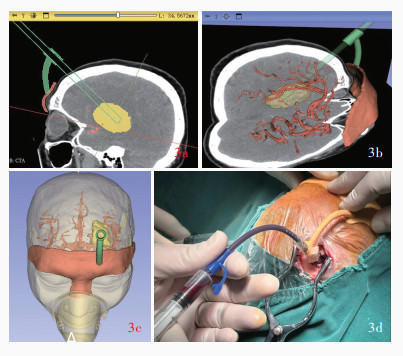

Zhou L , Xu G , Liu K , Zhang H , Lei P , Lu M , Song P , Li Z , Gao L , Hua Q , Chen Q , Cai Q . 3D Slicer combined with neuroendoscopic surgery for the treatment of basal ganglia hemorrhage after cranioplasty: a case report and literature review. Heliyon, 2024, 10: e37773.

doi: 10.1016/j.heliyon.2024.e37773